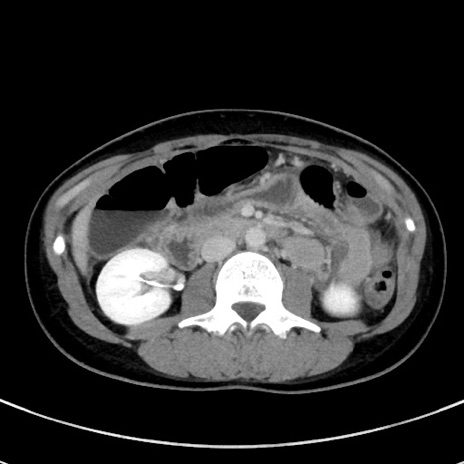

症例17(横断像)

【症例】20歳代女性

【主訴】嘔吐、下腹部痛

【現病歴】昨日夕食後に嘔吐し下腹部痛が出現。本日になっても嘔吐持続し改善しないため来院。

【身体所見】意識清明、BT 37.2℃、BP 108/67mmHg、腹部:平坦、やや硬、下腹部正中から右にかけて圧痛あり、反跳痛軽度あり、tapping pain(+)。

【データ】WBC 13600、CRP 14.94